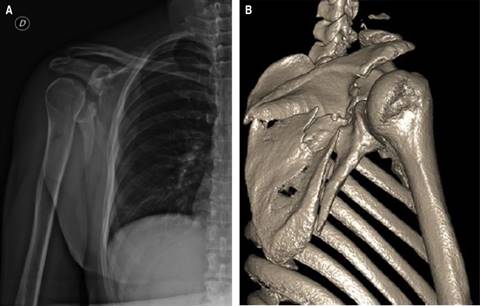

Paciente sin antecedentes patológicos diagnosticados, presentó accidente de tránsito de alta enérgica con fractura a nivel de escápula derecha (Figura 1). Fue llevado a manejo quirúrgico operatorio con reducción abierta de fractura más fijación interna. Presentó episodio de dolor intenso calificado en la escala numérica del dolor (numeric rating scale [NRS]) de 10 en zona de hombro y escápula derecha, se manejó con morfina 8 mg, diclofenaco 75 mg, dipirona 2 g en forma endovenosa, con mejora de dolor durante 30 minutos. Refirió recurrencia de dolor a intensidad en NRS de 10.

Figura 1: A) Radiografía de hombro derecho. B) Reconstrucción 3D de miembros superiores y articulaciones. Se aprecia fractura conminuta de la escápula con múltiples trazos de fractura, con trazos a nivel de la región inferior a la espina; fractura a nivel de la base de la apófisis coracoides, trazos de fractura a nivel del borde superior de la cavidad glenoidea.